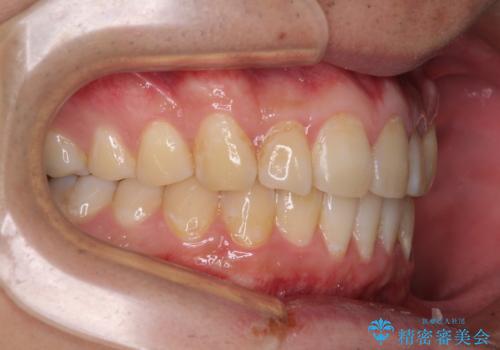

- 上下前歯のデコボコを気にして来院された患者様です。

前歯のデコボコ以外に左側の奥歯の咬み合わせに問題がありましたが、価格を抑え、短期間で気になる前歯を治したいとのことでした。

写真より左側臼歯の咬合がタイトではないことが分かりますが、こちらは保定期間に徐々に咬合させていくこととしました。